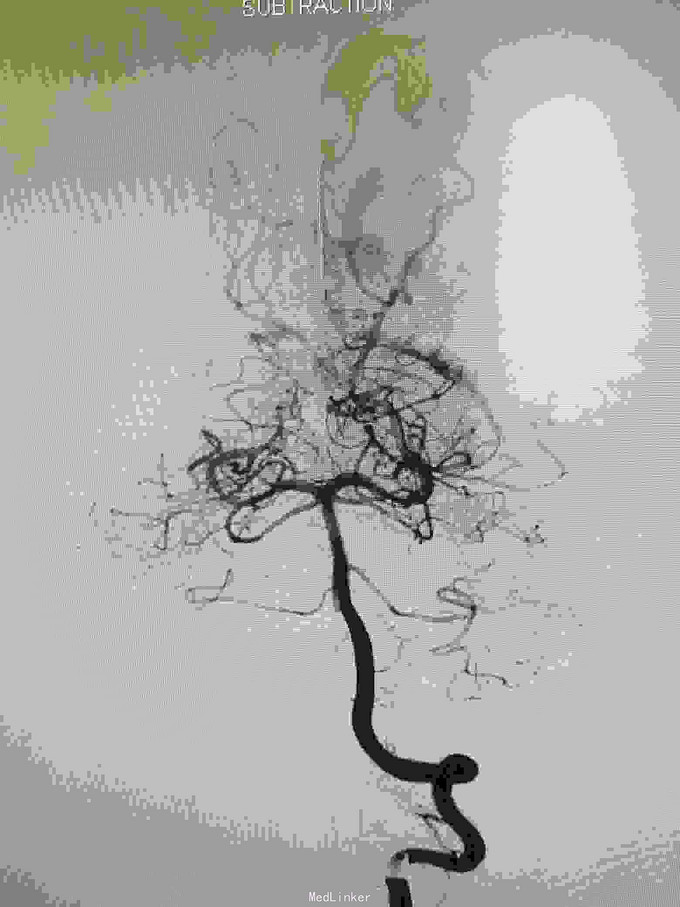

左枕顶区AVM。 左大脑后及左大脑前供血,深部静脉回流。

AVM治疗如能栓塞治疗创伤较小,手术切除虽较完全,但损伤是不可突视的问题。